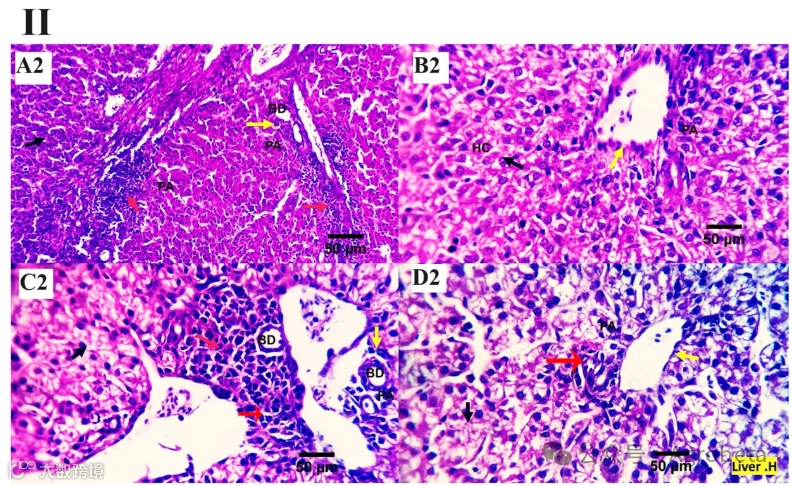

各个治疗组(0、200、400、600mg/kg微生物发酵溶菌酶(MMUR))的肝切片检查结果显示,各种结构均具有典型的组织学特征,包括门管区和肝细胞,这些肝细胞在中央静脉周围呈小团块状。肝门管区周围可见数个圆形细胞,表明存在自然免疫反应(图1)。对照组可见轻度至中度门管淋巴浆细胞聚集和胆汁增生(图1A)。在400mg/kg和600mg/kg微生物发酵溶菌酶(MMUR)水平下可见轻度聚集的免疫反应性淋巴浆细胞(图1C、D)聚集的炎症细胞似乎是一种免疫监视和保护装置,而不是一种破坏性的炎症程序(图1)。

图1.(I、II)各鸡实验组肝脏的显微照片((I):H&E×100放大倍数,(II):H&E×400放大倍数),这些实验组接受了0mg/kgMMUR(A1、A2)、200mg/kgMMUR(B1、B2)、400mg/kgMMUR(C1、C2)和600mg/kgMMUR(D1、D2))。这些显示了各种结构的典型组织学特征,包括门管区(PA,黄色箭头)和肝细胞(HC,黑色箭头),它们被视为围绕中央静脉(CV)的小肿块,在门管区周围观察到一些圆形细胞,表明存在自然免疫反应。在组(A)中检测到轻度至中度门管淋巴浆细胞聚集(红色箭头)和胆汁增生(BD,黄色箭头)。在组(C、D)中可以观察到轻度聚集的免疫反应性淋巴浆细胞(红色箭头)。